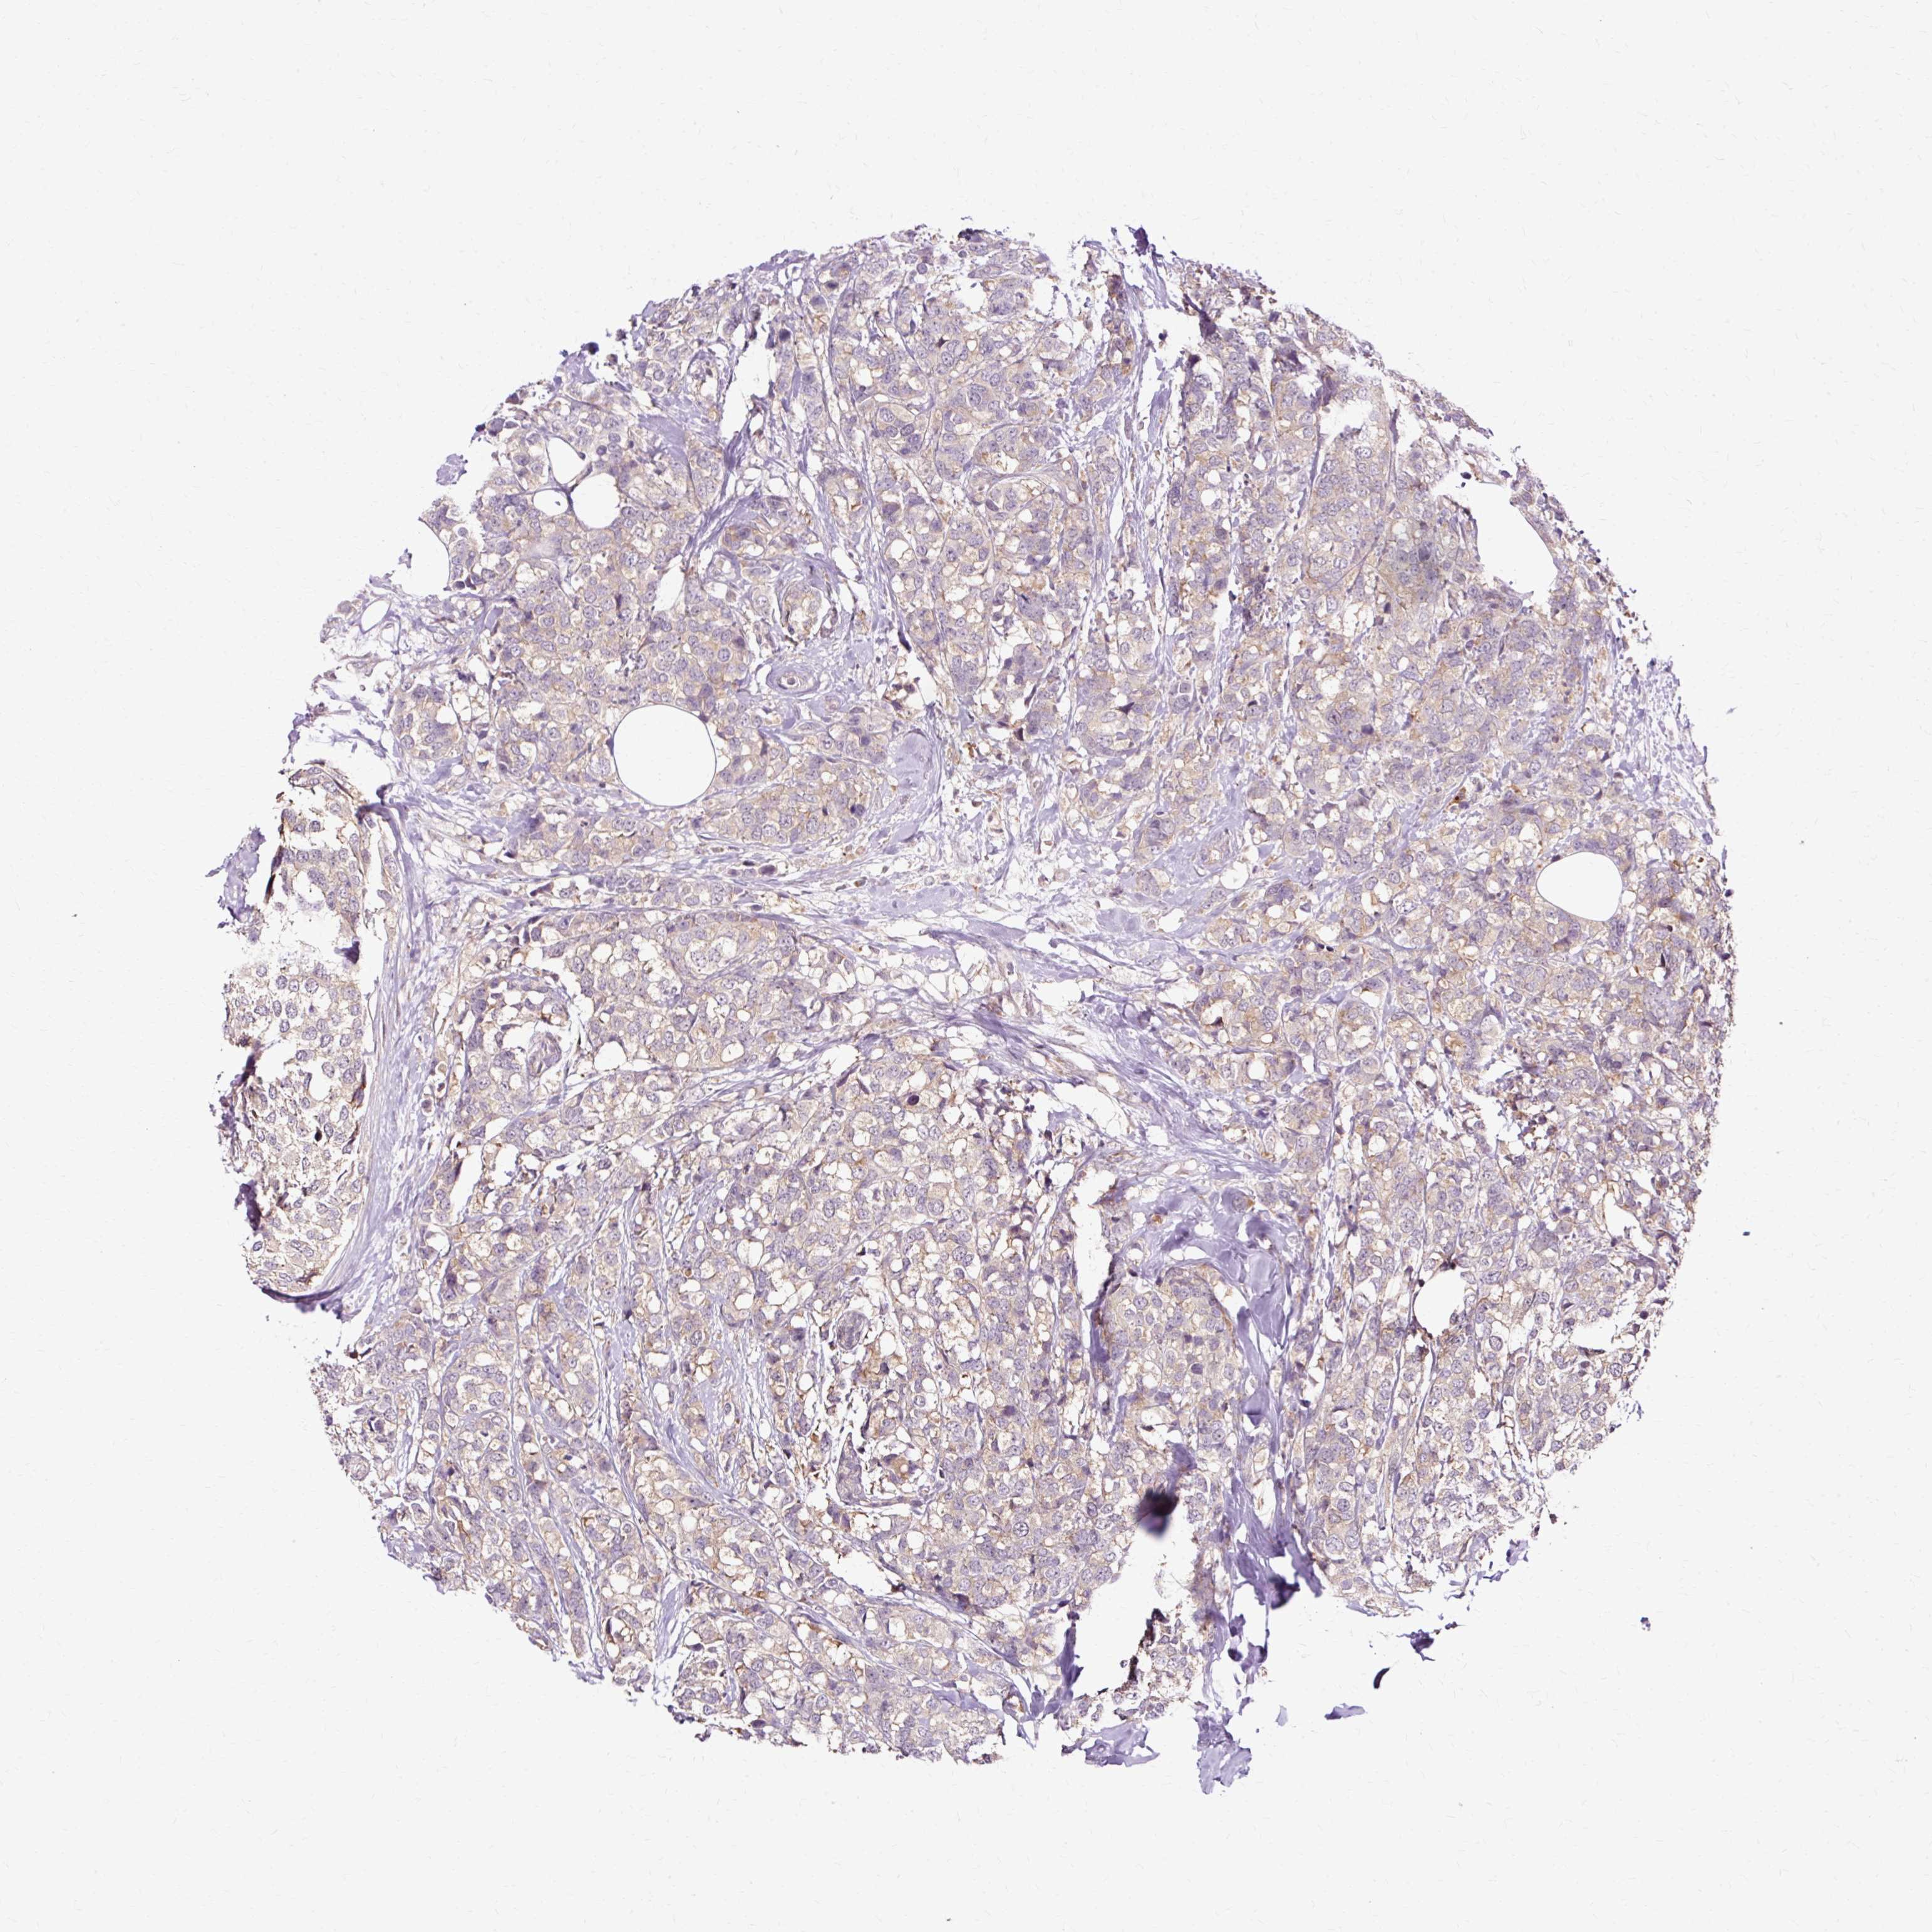

CANCER BREAST CANCER Show tissue menu

BRCA TCGA BRCA VALIDATION PROTEIN EXPRESSION

ANTIBODIES

AND

VALIDATION